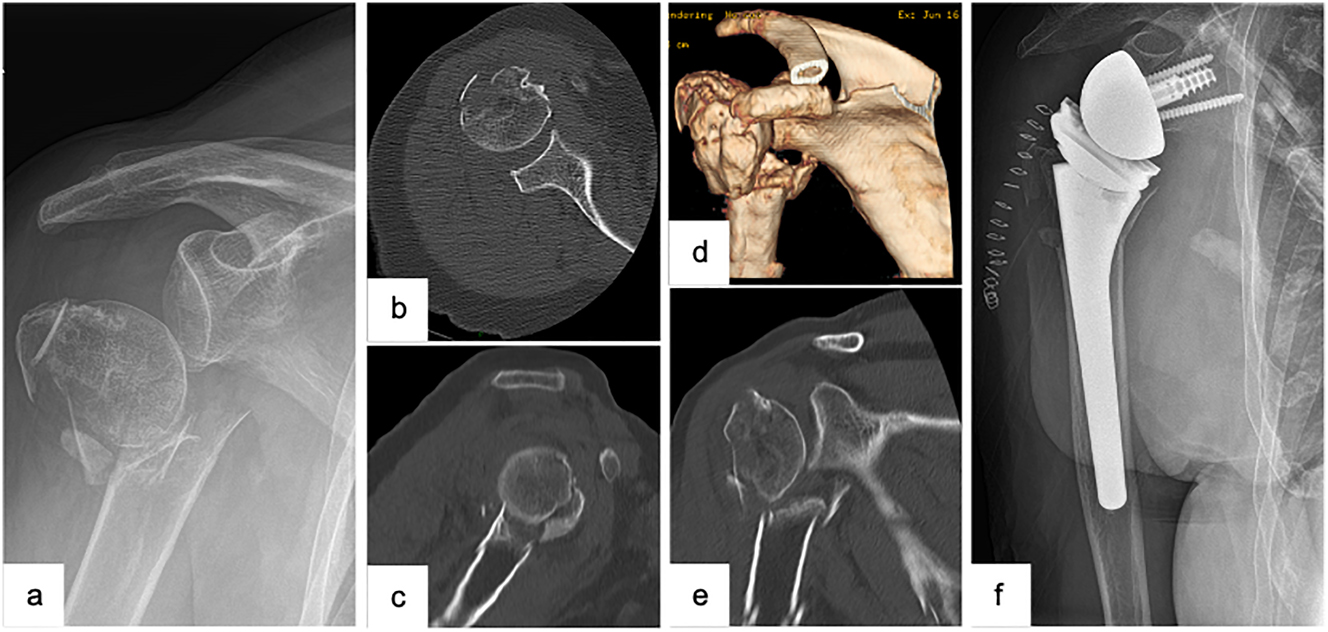

Another option to increase the stability of the reduction of complex fractures is the appliance of an additive support via a second, ventrally positioned plate (Figure 2). Apart from fractures with a reduced bone density, the latter is in particular crucial to highly instable fractures (e.g., fractures with a severely dislocated greater tuberosity, varus dislocated fractures with an insufficient medial support, fractures with a metaphyseal comminution zone). Both biomechanical and clinical results have so far shown promising results with respect to the use of an additive second plate [32].

Male patient (53 y), right shoulder, valgus impacted 4-part proximal humerus fracture (preoperative (3D-) CT-scan: a – 3D-CT-reconstruction, b – axial, c – coronal), open reduction and internal fixation with a laterally positioned locking plate osteosynthesis and a second, supportive, ventrally positioned plate to stabilize the lesser tuberosity (postoperative X-ray: d – a.p., e − Y-plane), complete removal of the double plate osteosynthesis and arthroscopically assisted arthrolysis (postoperative X-ray: f – a.p.).